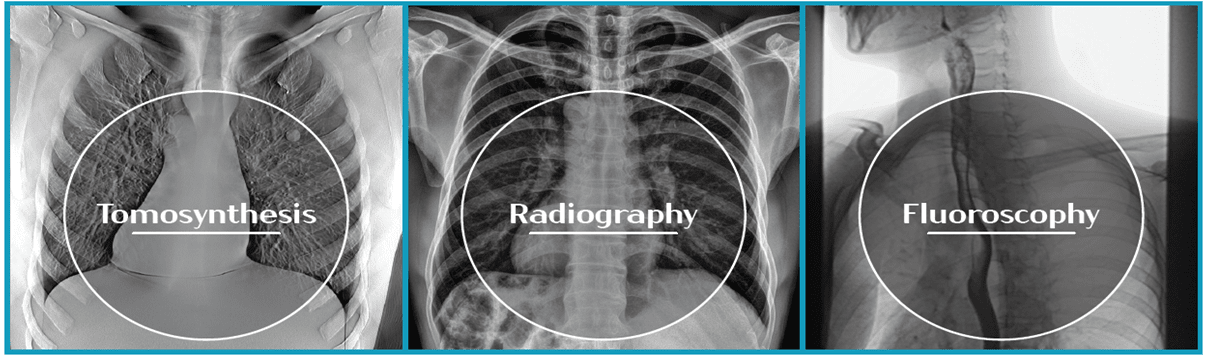

X-ray imaging method based on the reconstruction of sequential

images (tomograms) with a fixed distance between slices

· Without overlaying radiography projections

· Significantly lower radiation dose compared to CT

· When CT is excessive or unavailable

· Metal artifacts minimization

· Weight bearing examination

· Cost minimization compared to CT

Lung Cancer

Foot Fractures

| Diagnostics area | Type of diagnostics |

|---|---|

| Lung | Pneumonia, tuberculosis, malignancies |

| Musculoskeletal | Bone fracture, erosion, osteoid osteoma, malignancies |

| GIT | GIT contrast studies of the gastrointestinal tract, pathology of the kidneys, urinary systems |

| ENT | Pathologies in the paranasal sinuses |